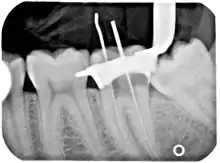

Another common complication of root canal therapy is when the entire length of the root canal is not completely cleaned out and filled (obturated) with root canal filling material (usually gutta percha). On the other hand, the root canal filling material may be extruded from the apex leading to other complications. The X-ray in the right margin shows two adjacent teeth that had received bad root canal therapy. The root canal filling material (3, 4, and 10) does not extend to the end of the tooth roots (5, 6 and 11). The dark circles at the bottom of the tooth roots (7 and 8) indicated infection in the surrounding bone. Recommended treatment is either to redo the root canal therapy or extract the tooth and place dental implants. Poor quality filling material or sealant may also cause root canal treatment to fail.[46]